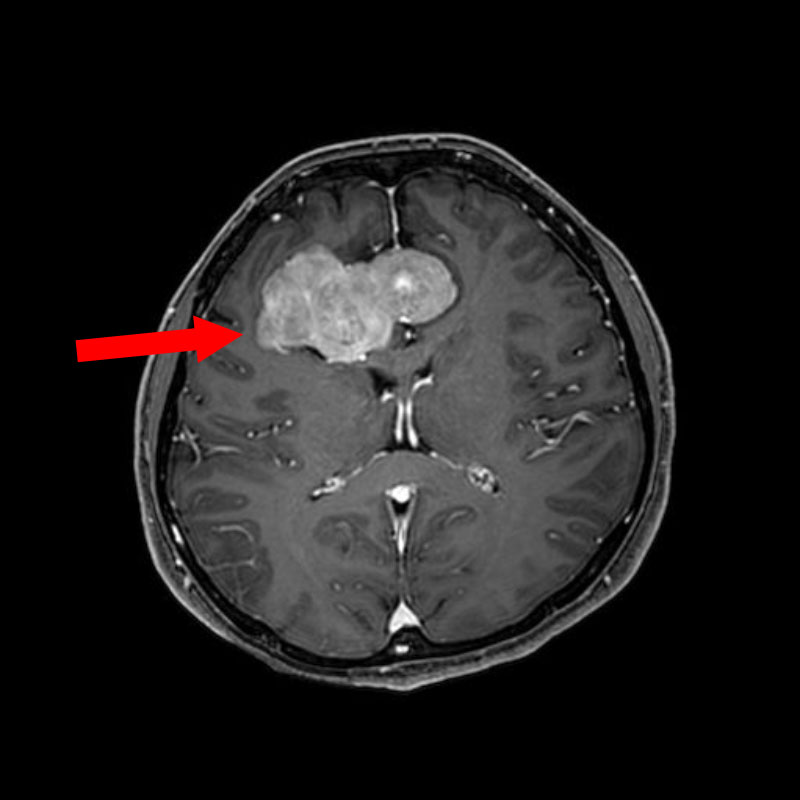

No.’25_110 手術前1

No.’25_110 手術前2